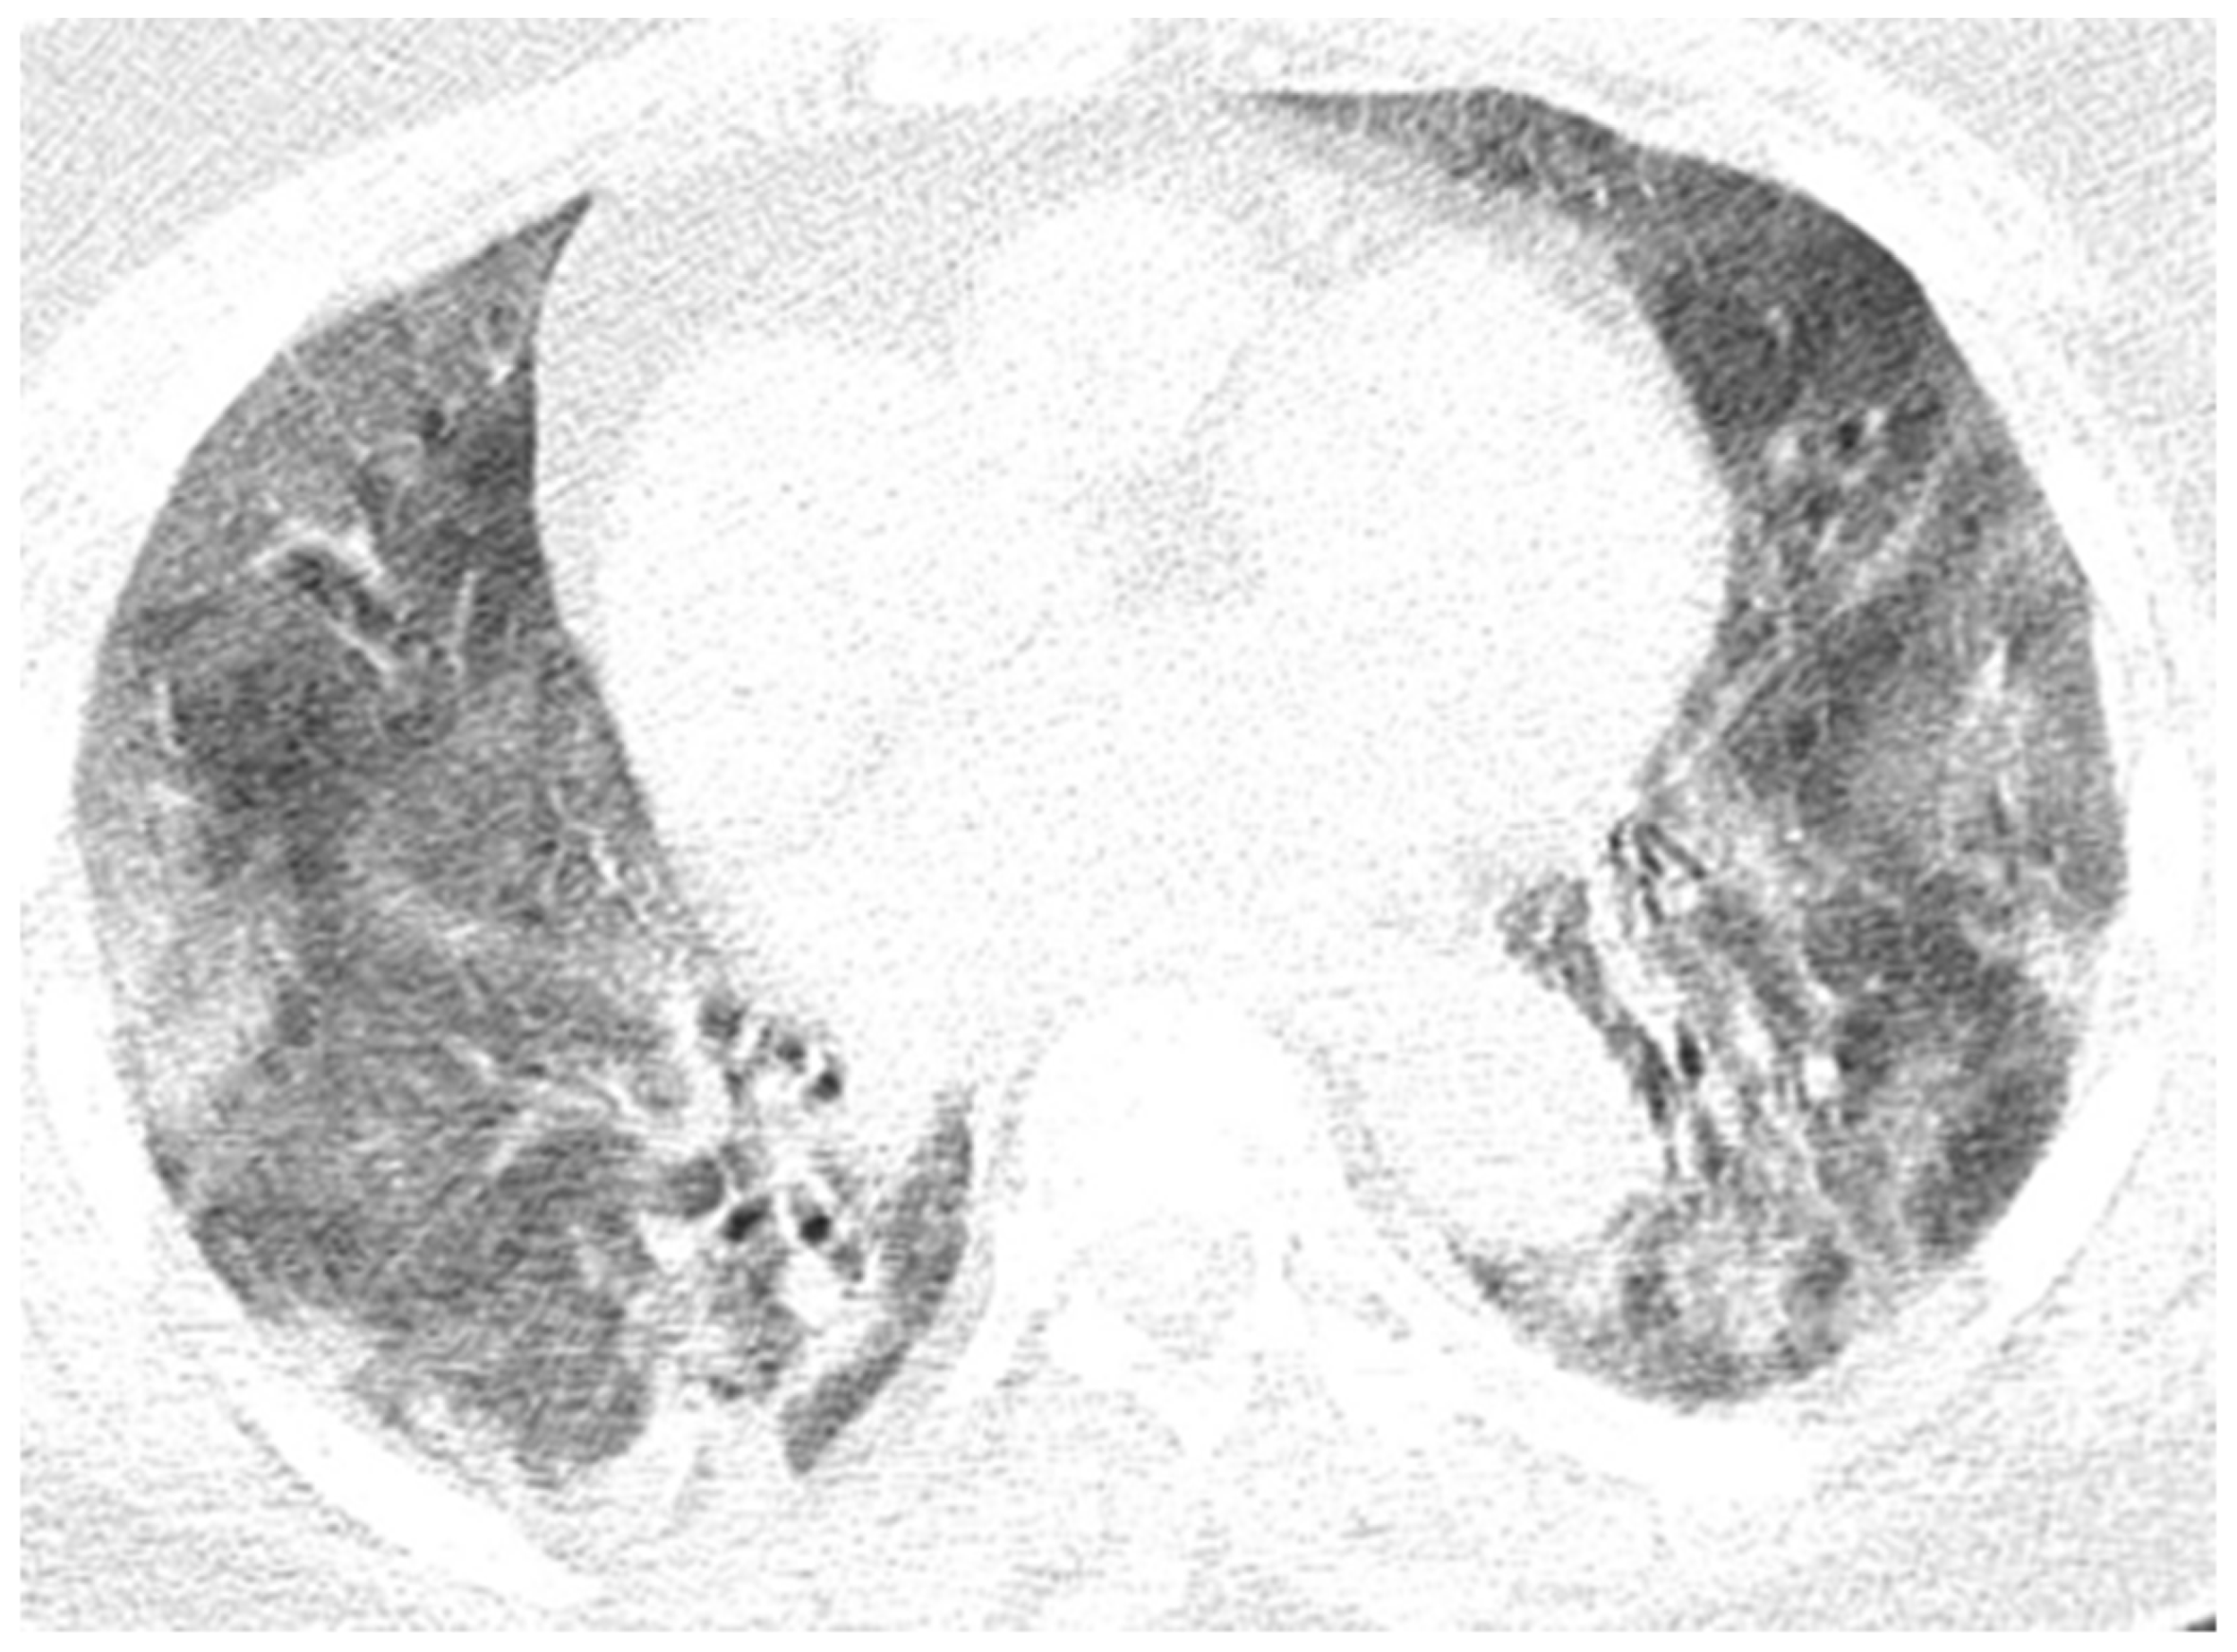

Figure 11. In evolution, CT images of the Case 10 patient show important numerical and dimensional progression of pulmonary lesions randomly distributed on more than 70% of the entire surface of both pulmonary fields. In conclusion, bilateral pulmonary condensations of SARS-CoV-2 type were in progress, with a severity score of 20 (13 at previous examination) and were determined to exhibit a severe degree of disorder.